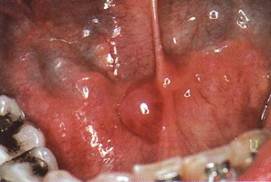

Слизистая ретенционная киста

Чаще образуется в малой железе нижней губы, реже щеки, переднего отдела дна полости рта, нижней поверхности языка и на небе. Преимущественная локализация на нижней губе связана с ее частым травми­рованием зубами.

Клиника. Киста располагается под слизистой оболочкой, имеет вид полуша­ровидного возвышения с четкими границами с голубоватым оттенком. Иногда слизистая оболочка над ней белесоватого цвета за счет рубцовых изменений вследствие травмы. Пальпаторно киста эла­стичной консистенции с зыблением, безболезненная. Прикусывание; слизистой оболочки над кистой может привести к опорожнению с вы­делением прозрачной тягучей жидкости. При инфицировании содер­жимого, что встречается редко, возникает воспаление.